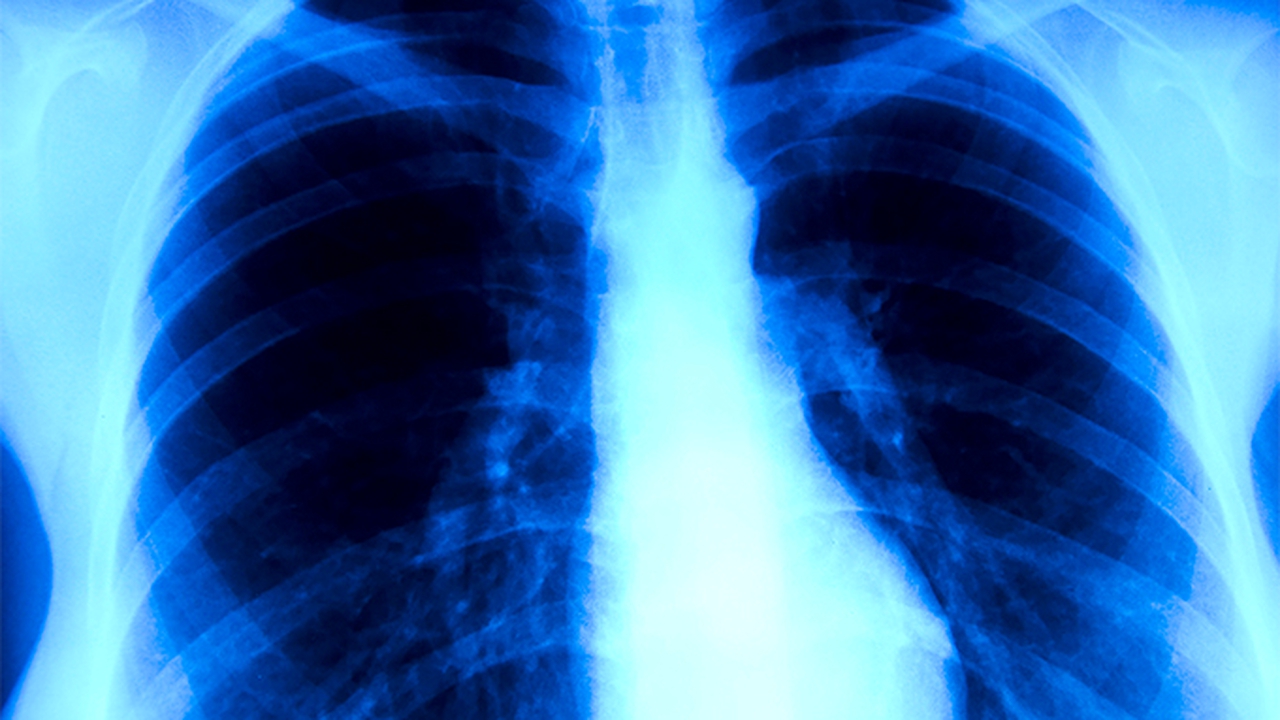

山東省腫瘤醫院是山東省內專(zhuān)注于腫瘤防治的專(zhuān)科醫院,擁有的腫瘤診斷設備和專(zhuān)業(yè)的醫療團隊。醫院在腫瘤早期篩查、診斷和綜合治療方面具有顯著(zhù)優(yōu)勢,尤其在肺癌、乳腺癌、胃癌等常見(jiàn)腫瘤的診治上積累了豐富經(jīng)驗。

山東大學(xué)齊魯醫院腫瘤中心是山東省重點(diǎn)學(xué)科,集醫療、教學(xué)、科研于一體。醫院擁有PET-CT、MRI等高端影像設備,能夠實(shí)現腫瘤的早期診斷。腫瘤中心在分子靶向治療、免疫治療等前沿領(lǐng)域具有突出優(yōu)勢。